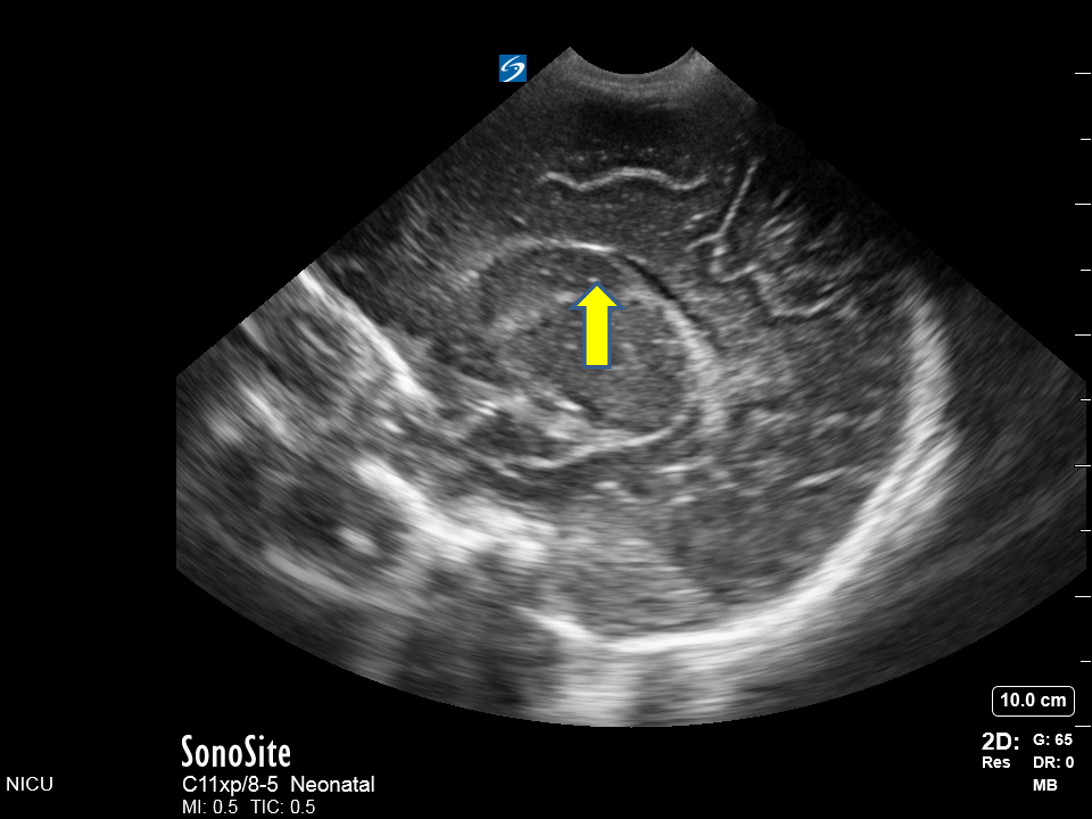

Neonatology Grade 1 IVH Image